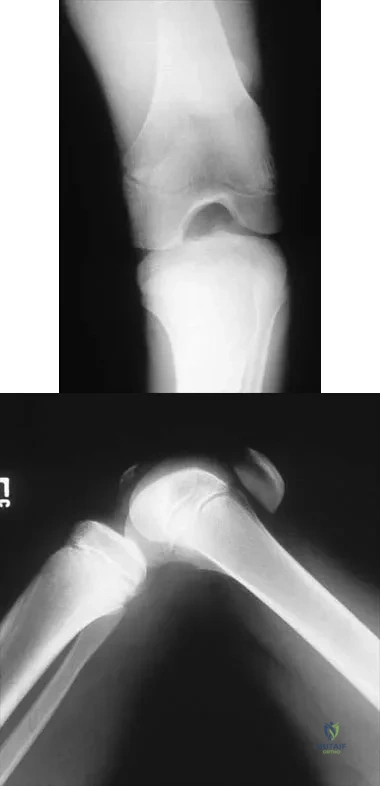

Question 5

A 63-year-old woman reports giving way of the knee and pain after undergoing primary total knee arthroplasty (TKA) 1 year ago. Examination reveals that the knee is stable in full extension but has gross anteroposterior instability at 90 degrees of flexion. The patient can fully extend her knee with normal quadriceps strength. Studies for infection are negative. AP and lateral radiographs are shown in Figures 12a and 12b, respectively. What is the appropriate management?

Explanation